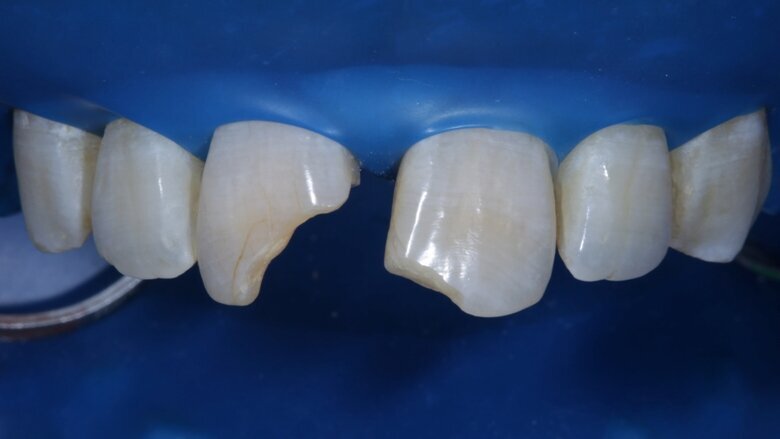

The two maxillary central incisors were fractured and non-vital with noticeable darkening of shade [ Fig 1,2 ]. They were mal-aligned buccolingually and there was a midline diastema as well . There was no tenderness on percussion. There were peri-apical lesions associated with both incisors in the radiograph.

Non-surgical endodontic treatment was done in the 1st week. After the symptoms resolved completely we were ready to restore form, function and aesthetics. Non-vital in-office bleaching was done. Pola office bleach was used for the same, 3 cycles of 8 minutes each. It appeared that the shade had corrected completely after bleaching but we waited for it to stabilize.

Two weeks later, the shade [ Fig 3 ] stabilized and the teeth were ready for bonding. We observed that the central incisors were still darker than the neighboring teeth. Direct composite veneers were planned with the help of a lab made wax up [ Fig 4 ] and a putty index. Bevels were placed and most of the preparation was in enamel. After the total etch protocol, 5th generation bonding agent was used. 3M Z350XT shades were used for the build up. A2 Enamel shade was used for the palatal shell [ Fig 6 ] and the proximal walls [ Fig 11 ].